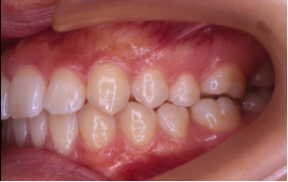

過蓋咬合(かがいこうごう)※ 非抜歯

20歳/女性

悩み:噛み合わせが深い

下の前歯が上の歯茎に食い込んでいる状態

治療期間:約2年

治療前

治療後

深い噛み合せを改善する治療が必要になりました。

先に深い噛み合せを上げないと矯正装置がつかないので、噛み合せの深さを改善する治療から行なう矯正治療となりました。